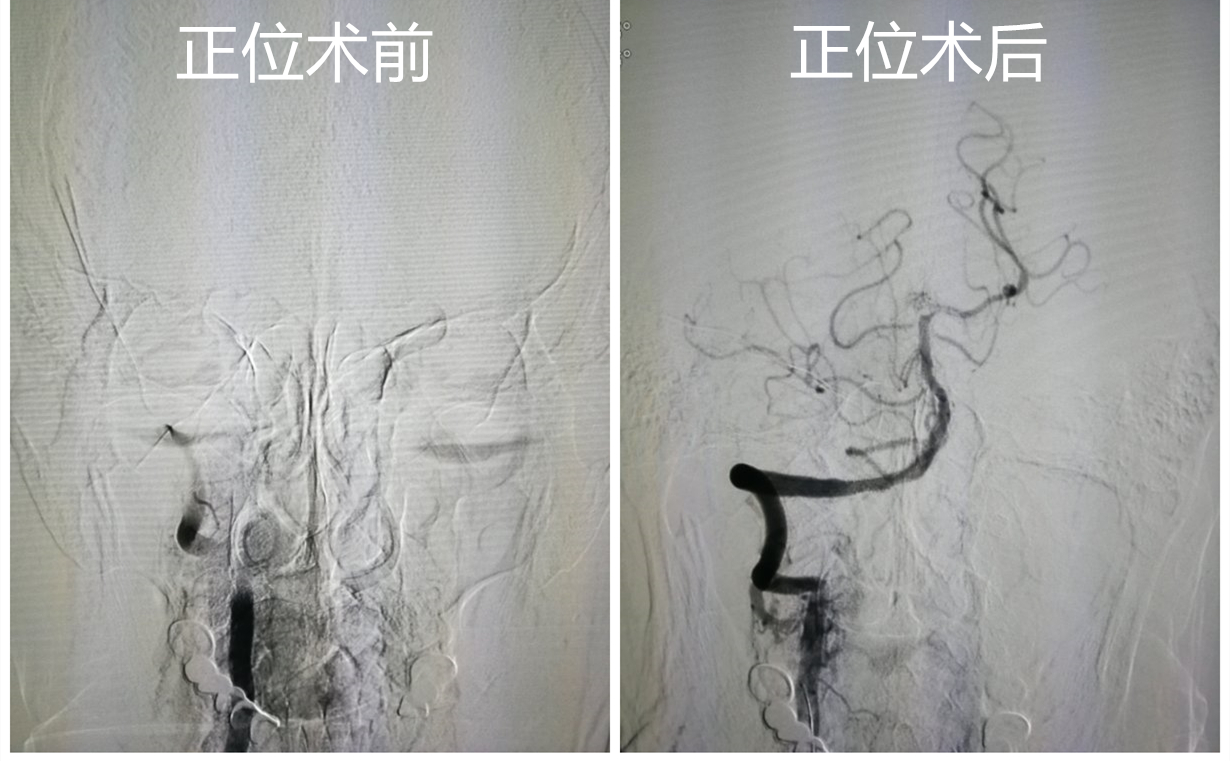

患者王某,男,73岁,头晕5.5小时,休息后未缓解,半小时后出现言语笨拙,速来我院急诊诊治,急查头MRA+DWI显示右侧小脑新发脑梗死,椎基底动脉显影不良,急诊立即给予血管内治疗,同时收入我院神经内三科。患者王某入院1小时后出现意识障碍,徐鹏医生紧急为患者行主动脉弓+全脑血管造影术+椎动脉取栓术+椎动脉球囊扩张支架植入术。术后患者复查造影可见狭窄消失,血运良好。